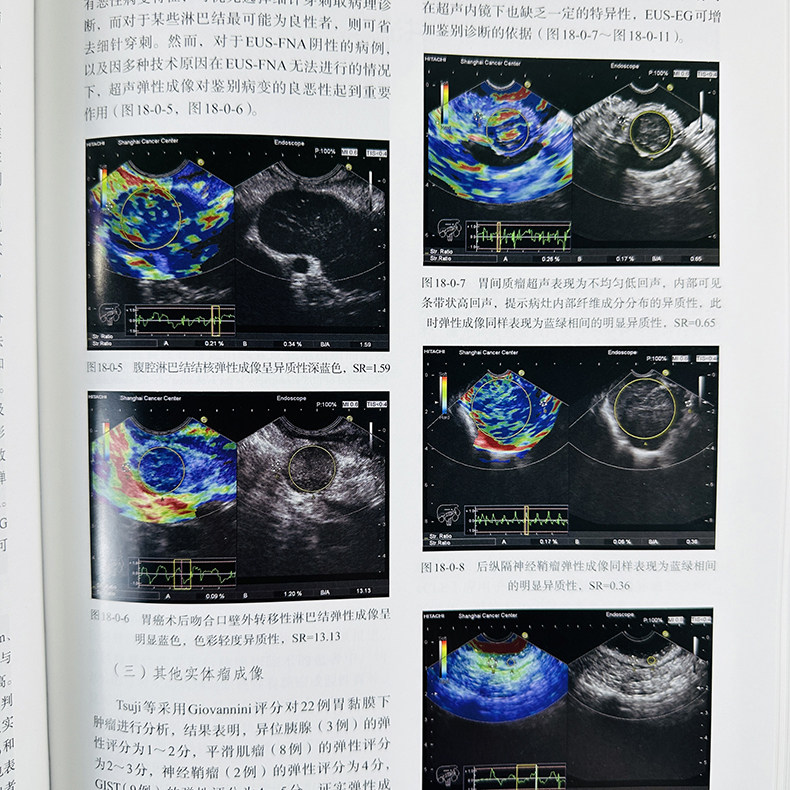

第十八章 超声内镜弹性成像 215